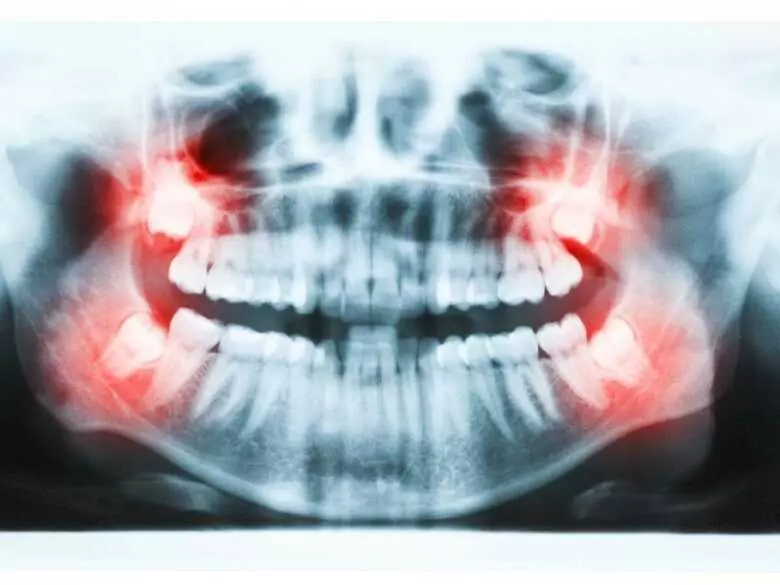

PantherMedia

Prześwietlenie zębów